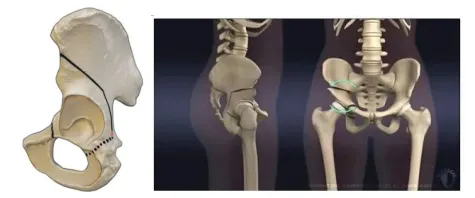

髖臼周圍截骨術(shù)模擬圖